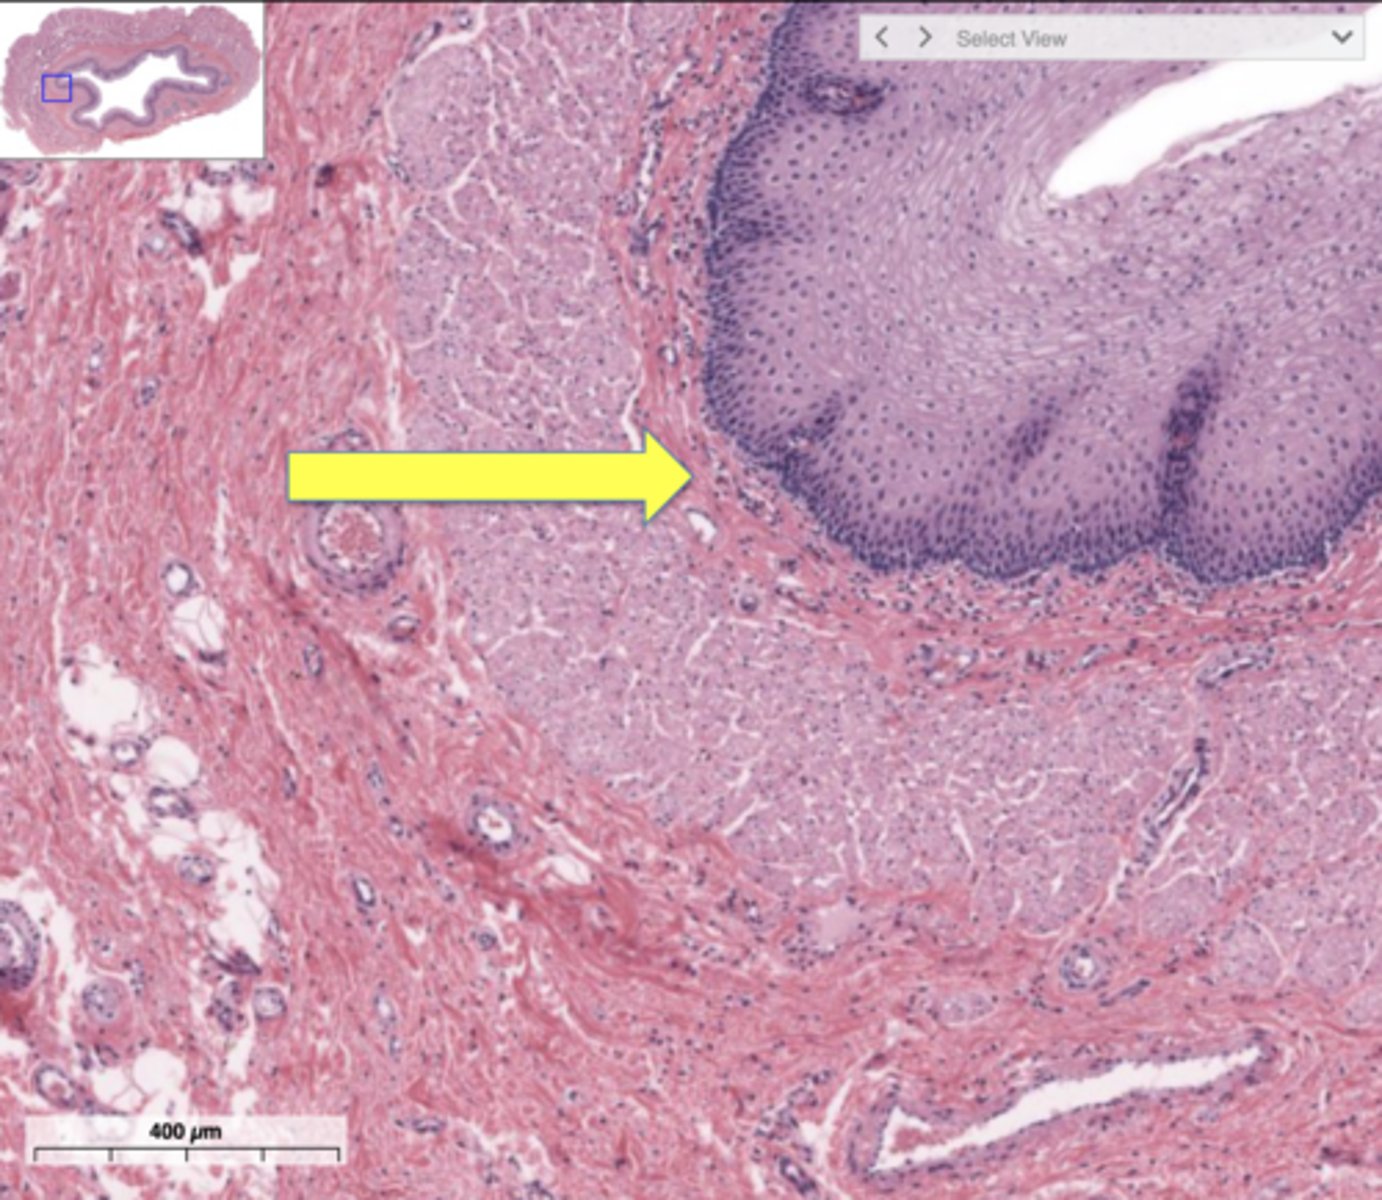

Which organ is this?

Kidney